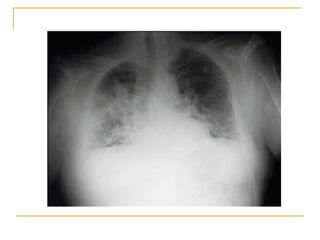

Historia Clínica Paciente de 36 años de edad, HIV (+), homosexual, sin tratamiento retroviral, sin profilaxis antibiótica, antecedentes de haber sufrido 4 episodios de neumonía, uno con derrame pleural. Una semana antes de su ingreso consultó por tos irritativa, fiebre, calofríos, dolor en el centro del tórax y disnea progresiva. Al ingreso, se encontraba polipneico, hipotenso, afebril Al examen físico existía candidiasis oral y crepitaciones en ambos campos pulmonares. El hemograma mostró anemia, leucopenia, Linfocitos T CD4 23%  Se efectuó fibrobroncoscopía con lavado broncoalveolar, que mostró tinción y PCR positivas para  Pneumocystis carinii.

Extenso enfisema buloso en los lóbulos superiores de ambos pulmones.

Hacia las bases hay aumento de la densidad radiológica

En la base derecha se observan imágenes quísticas